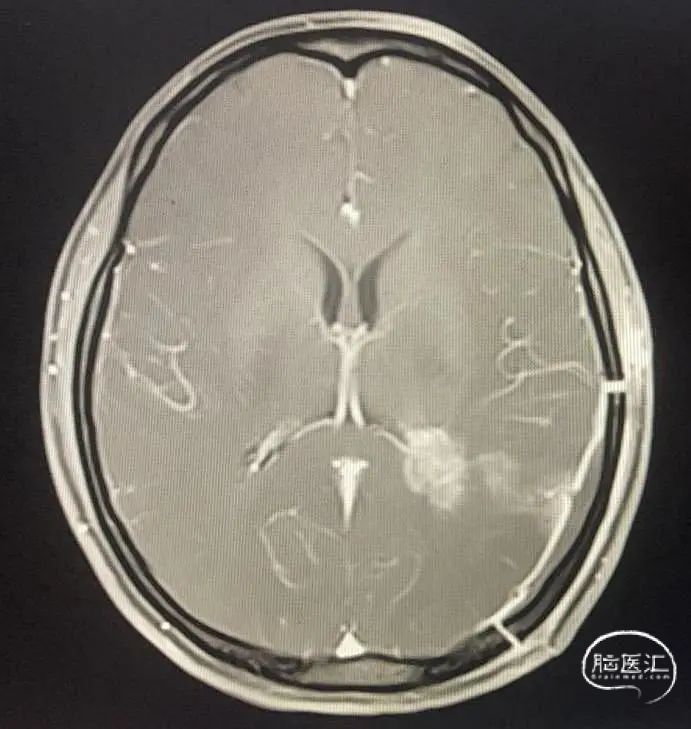

图1

图2